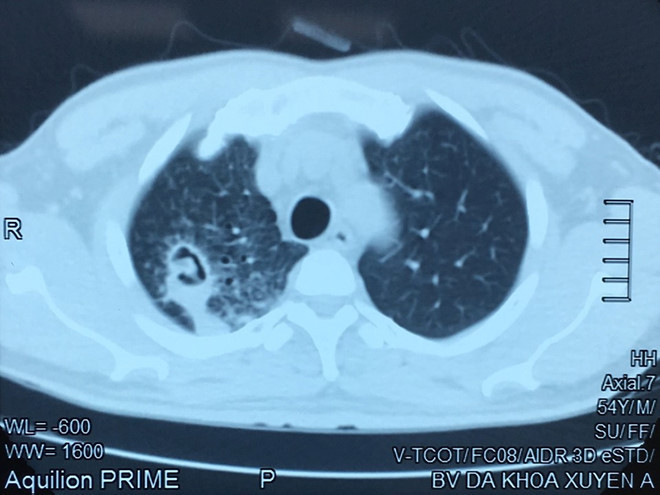

Tại Bệnh viện đa khoa Xuyên Á, qua khám lâm sàng và chụp CT scanner lồng ngực, các bác sĩ phát hiện tổn thương do nấm khu trú ở thùy trên phổi phải, kèm tổn thương thâm nhiễm. Với triệu chứng này bác sĩ nghĩ bệnh nhân chắc chắn bị tổn thương do nấm gây ho ra máu. Kết quả các mẫu xét nghiệm đàm xác định bệnh nhân không bị lao.